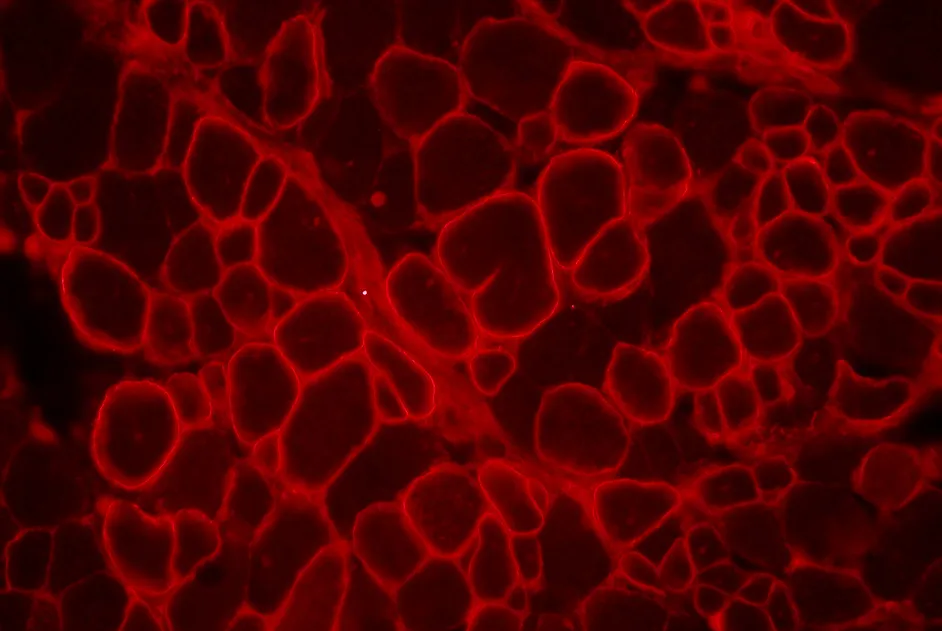

Les résultats publiés en juillet 2011 dans le journal The Lancet sont très encourageants : le traitement est bien toléré et les analyses ont montré chez 7 participants, une nouvelle production de dystrophine, de manière significative et dépendante de la dose injectée. Les 3 personnes avec les meilleures réponses présentent jusqu’à 15%, 21% et 55% de fibres exprimant la dystrophine après traitement. Par ailleurs, les chercheurs ont montré que cette dystrophine ainsi produite fonctionne correctement dans le muscle et qu’elle n’entraine pas de réponse immunitaire.